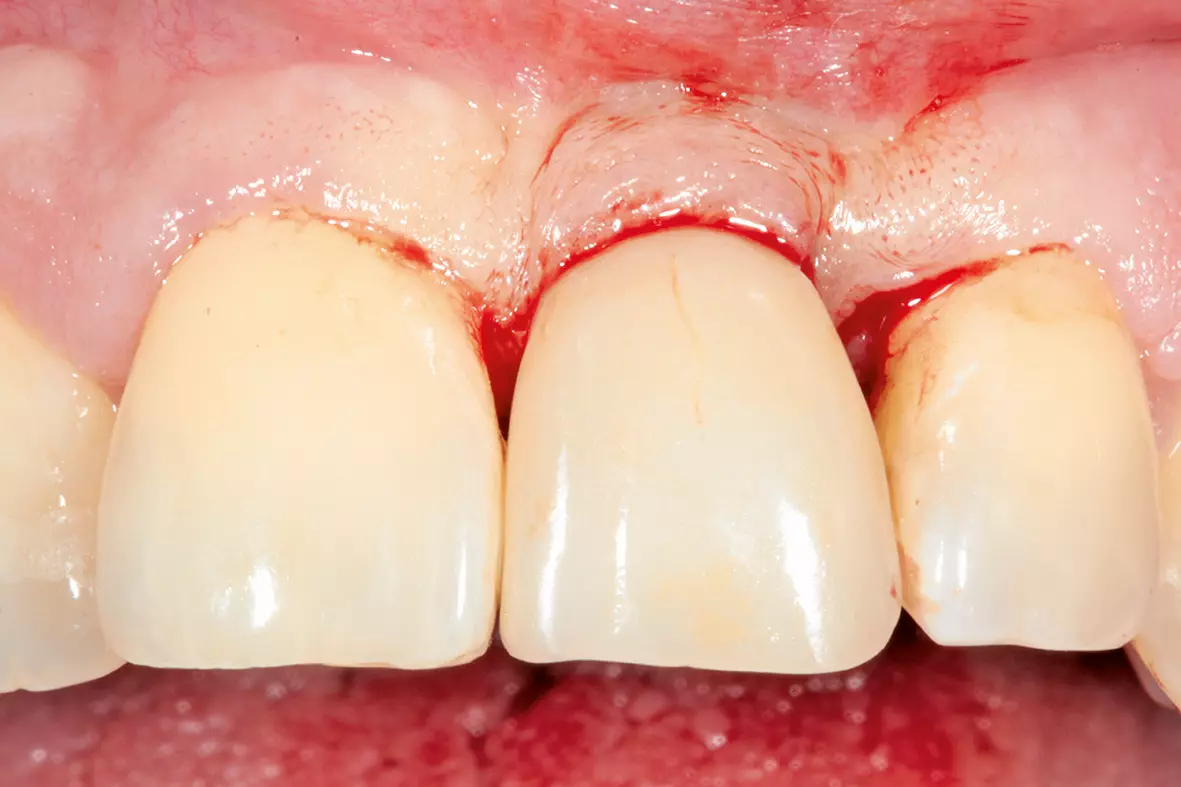

Nach drei Monaten folgte die Freilegung (Abb. 17). In der Operation erfolgte zunächst unter dem Mikroskop wieder die krestale Schnittführung an derselben Stelle wie bei der Implantation unter Erhalt eines einige Millimeter breiten Streifens befestigter Mukosa. Dann wurde der Lappen mit einem Papillenraspatorium zuerst etwas angehoben und dann scharf epiperiostal weiterpräpariert. Die Verschlussschraube wurde aus dem Implantat entfernt und die provisorische Krone eingegliedert. Der interdentale Wundverschluss erfolgte mit Prolene 6.0 (Ethicon, Johnson & Johnson Medical) in Form von vertikalen Matratzennähten (Abb. 18).